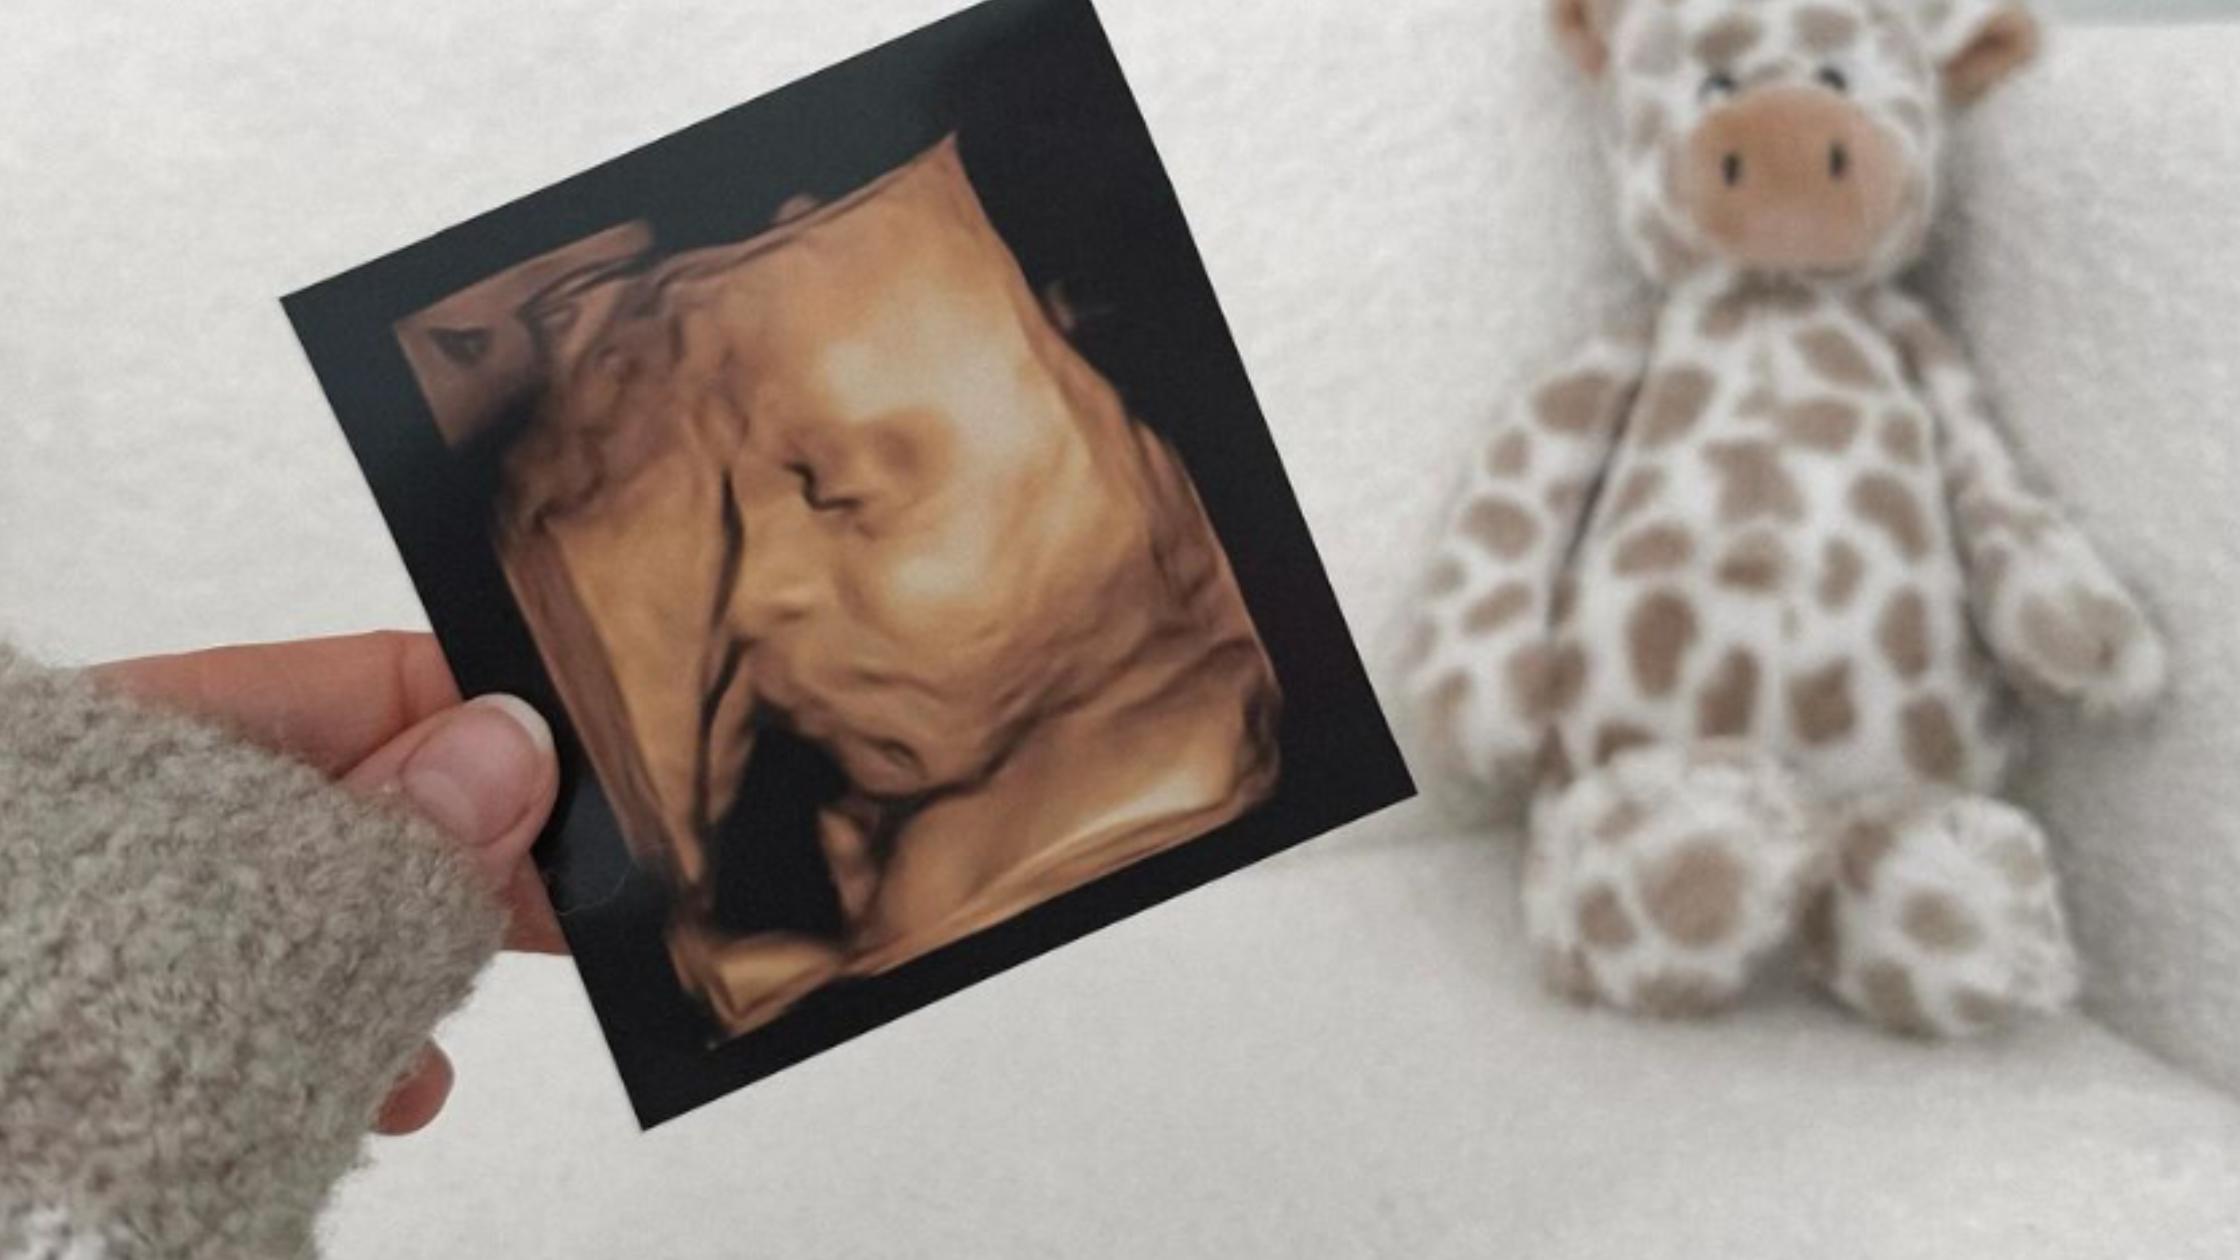

Take a Peek at Your Baby: The Benefits of 4D Scans at Our Clinic

There’s nothing quite like the moment when you see your baby on screen – and thanks to 4D ultrasound scanning, that moment is more magical